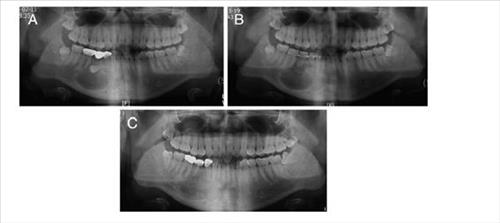

ÀÕ¸ö»À ¾ø´Â ȯÀÚ¿¡°Ô ÀÚ°¡Ä¡¾Æ ÀÌ½Ä ¼º°ø

°³²¼¼ºê¶õ½ºº´¿ø ÀÇ·áÁø, ¼ö¼ú °á°ú Àú¸í ÇмúÁö¿¡ (¼¿ï) Àü¸íÈÆ ±âÀÚ = ±¹³» ÀÇ·áÁøÀÌ Ä¡¾ÆÀÇ ¸Åº¹ »óÅ ¶§¹®¿¡ ÀÕ¸ö»À°¡ °ÅÀÇ ¾ø¾î Ä¡¾Æ À̽ÄÀÌ ¾î·Æ´ø ȯÀÚ¿¡°Ô ÀÚ°¡ Ä¡¾Æ¸¦ À̽ÄÇÏ´Â ¼ö¼ú¿¡ ¼º°øÇß´Ù. ÀÌ...